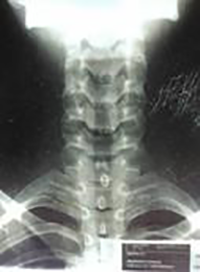

Se indica realizar resonancia magnética, evidenciando la existencia de una lesión ocupante de espacio a nivel de C5-C6, de aspecto subdural. En vista de estos hallazgos, se procede a realizar laminectomía en C5-C6 con abordaje posterior en donde, posterior a incisión de la duramadre, se aprecia la existencia de una lesión quística. Se logra realizar exéresis completa de la misma, ya que no presenta adherencias a la médula espinal. La laminectomía se puede apreciar en la radiografía de la columna cervical postoperatoria (Figura 1).

Figura 1: Radiografía de columna cervical anteroposterior, donde se evidencia laminectomía en C5-C6 con abordaje posterior.